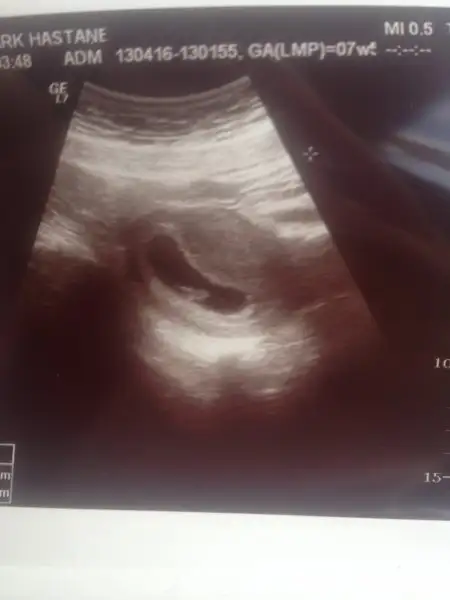

Bu ise yarar mi? Karindan. Bu arada etkilermi bilemiyorum ters rahim.Burda cok buyuk bana 6 -8 hafta arasi goruntu lazim :)

Karından cekildiyse erkek gibi canimEki Görüntüle 1814021 Arkadaşlar cinsiyet için tahmin alabilirmiyim 7+ 4

Kız gibidlrsordn canim benimkini yorumlarmisin. Tsk.

İnşallah canim, burda herkes erkek demişti ama kız mişNubu çok net sanki belki de ben yanlış yorumladım. Hayırlı sağlıklı bir evlat olur insalla